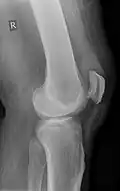

Quadriceps tendon rupture in plain X-ray -

Quadriceps tendon rupture in plain X-ray: Incomplete rupture with haematoma in tendon. -